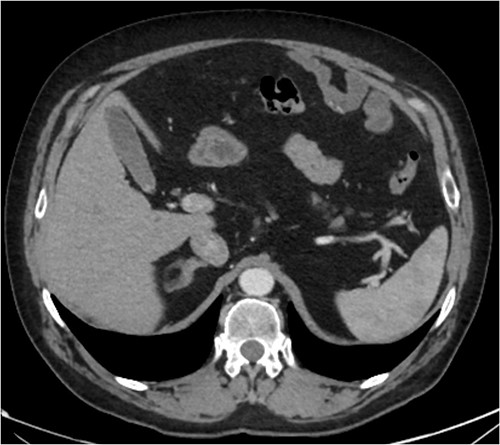

A CT abdomen-pelvis (CT-AP) revealed an acute haematoma inferolateral to the third part of the duodenum and another at the root of the mesentery. High density fluid related to the mesenteric bleed was also seen extending from the right para-colic gutter into the pelvis and in the peri-hepatic region. The patient was admitted under general surgery, stabilized with intra-venous fluid resuscitation, co-amoxiclav and metronidazole and cross matched for four units of blood. A CT-angiogram demonstrated acute haemorrhage throughout the abdomen with a 104 x 62 mm haematoma arising centrally at the level of L2 within the mesenteric fat (Fig. 1). The haematoma did not appear to originate from any specific mesenteric vessels but was related to some mid and distal jejunal loops. The angiogram also showed discontinuity when tracing the proximal and mid jejunal loops inferiorly, extensive haemorrhagic peritoneal fluid around the liver extending inferiorly (Fig. 2) and a small amount of peri-splenic haemorrhagic fluid. Curved reformatting of the angiogram revealed no abnormalities within the superior mesenteric artery (Fig. 3).

Curved reprogramming of the initial CT angiogram. Curved reprogramming of the patient’s initial CT angiogram showed no evidence of an aneurysm within the superior mesenteric artery, effectively ruling this out as a cause of the patient’s acute bleed.